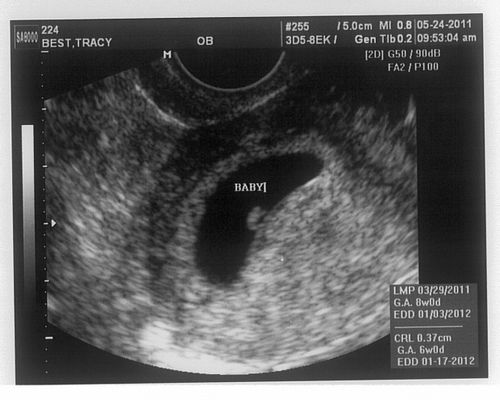

Фото плода на 6 тижні вагітності

УЗД на 6 тижні вагітності

УЗД на шостому тижні вагітності допомагає оцінити наявність вагітності, що розвивається, лікар використовує трансвагінальний датчик через те, що він дає більш чіткі дані. При ультразвуковому обстеженні збільшується розмір матки, вже розрізняються окремі частини тіла і органи плоду. Можна прослухати серцебиття малюка. На УЗД досі видно жовтковий мішок і жовте тіло в яєчнику.

УЗД по тижнях вагітності з фото допоможуть вам сформувати враження про розвиток плода.